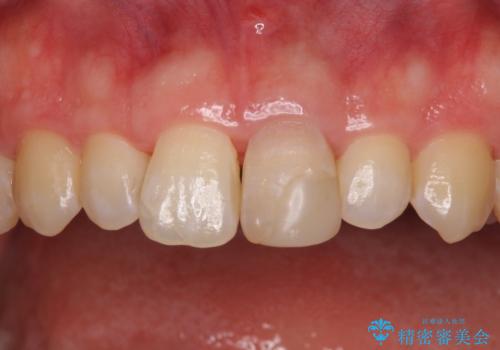

変色した前歯をオールセラミッククラウンに

- 転んだ際に欠けてしまった前歯の変色が気になるとのことで来院された患者様です。

診察やレントゲン写真より神経組織の失活が認められたため、根管治療、ファイバーコアによる土台築製後、オールセラミッククラウンにて補綴することとしました。

神経を取り除いた歯は時間とともに変色してきます。

クリーニングやホワイトニングでは改善できないため、オールセラミッククラウンなどによる補綴治療が必要となります。